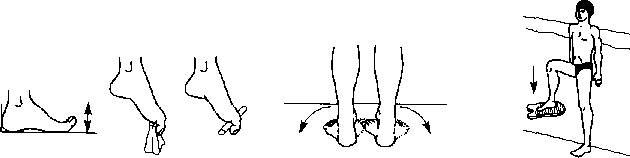

Примерный комплекс упражнений № 21, применяемый во втором периоде ЛФК при невритах большеберцового и малоберцового нервов

И. п. — стоя лицом к бортику, держаться за него руками. Приподняться на носки. 10 раз.

И.п. — тоже. Выполнять приседания с выдохом в воду (см. рис. 4.2). 10 раз.

Изучение дыхания у бортика (см. рис. 2.14, 4.2). 1 мин.

Упражнения в ходьбе (при необходимости — с опорой о бортик): на пятках, на носках, внутреннем и наружном краях стопы, с движениями руками, следить за правильным механизмом ходьбы. 1—2 мин.

Изучение движений ногами кролем, лежа на воде на спине, держась руками за бортик (см. рис. 4.2). Тоже, но на груди (см. рис. 4.18). 1 мин.

И. п. — стоя у бортика, выполнять всевозможные движения пальцами обеих ног. Больной ногой пытаться захватить мелкие предметы со дна. 1 мин (рис. 4.32, 7).

Плавание с помощью движений ногами кролем на спине и на груди с дыханием (см. рис. 2.13, 2.18). 25 м.

/ 2 3

Рис. 4.32. Примерный комплекс упражнений № 21, применяемый но втором периоде ЛФК при невритах большеберцового и малоберцового

нервов

И.п. — стоя лицом к бортику, держаться за него руками. Не меняя положения туловища, развернуть носки влево, вернуться в и. п. Затем — вправо. То же, но разводить носки в стороны. 1 мин (рис. 4.32, 2).

И. п. — стоя у бортика, изучение техники движений руками кролем, затем в ходьбе (см. рис. 2.19).

Плавание до 100 м кролем в ластах.

И. п. —стоя спиной к бортику, держаться за него руками. Поднять ноги и выполнять упражнение «Велосипед» (см. рис. 4.5). Стараться, чтобы в движении принимали участие стопы. 30 с.

И. п. — стоя на небольшой глубине на здоровой ноге, больной ногой (стопой) стараться «утопить» и удерживать под водой доску, круг. 30 с (рис 4.32, 3).

Игра «Водяной футбол» (см. рис. 4.19). Стараться бить по мячу (камере, заполненной водой) больной ногой. 2 мин.